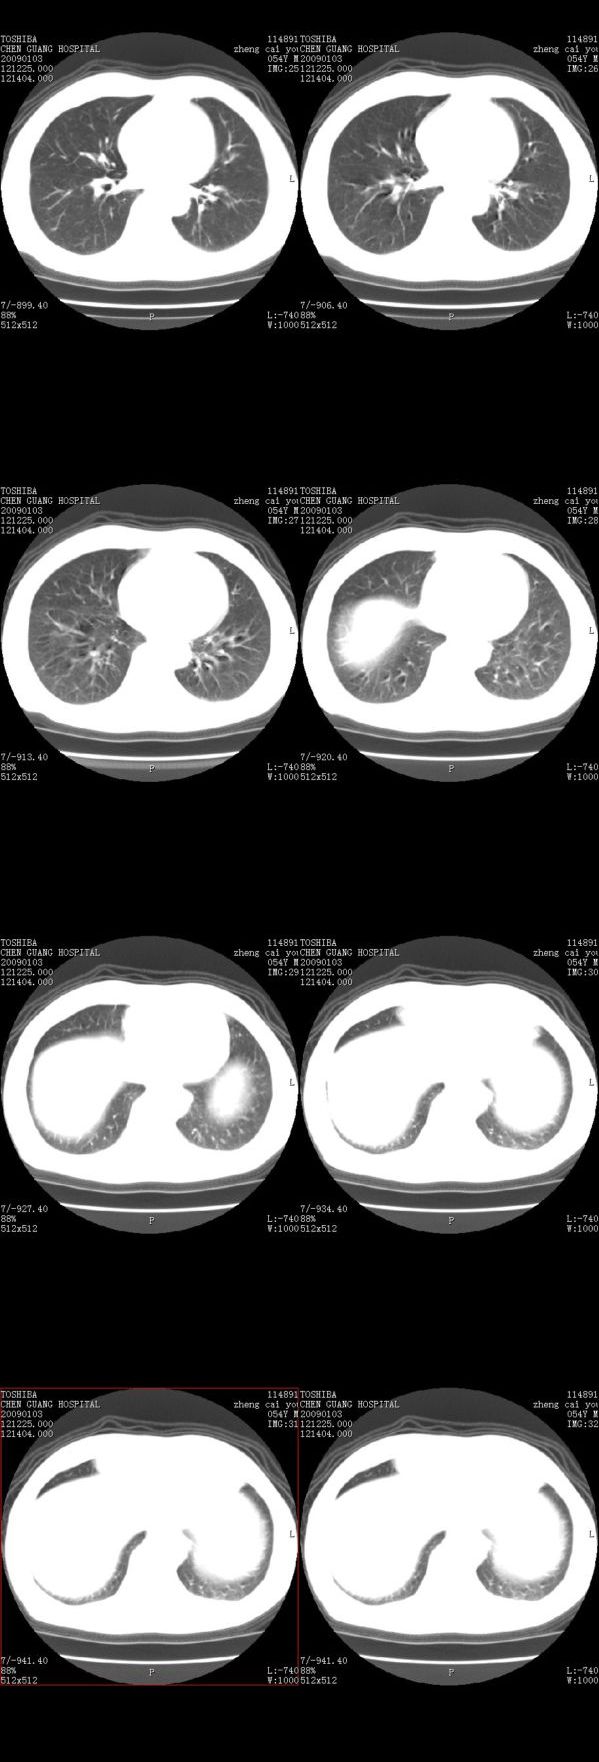

男,54岁,平时有吸烟后咳嗽、咯痰史,因右侧胸部(腋窝下)疼痛来检查平片,见右下肺动脉干起始处处结节,后到同学处做了平扫及增强。请各位老师帮忙看一下,不甚感谢!!!!!

小叶中心型肺气肿

肺窗薄扫、常规扫描均未见明确病变;右下肺门圆形与肺血管等密度影,考虑为血管变异;应该要纵隔窗才能进一步明辨。